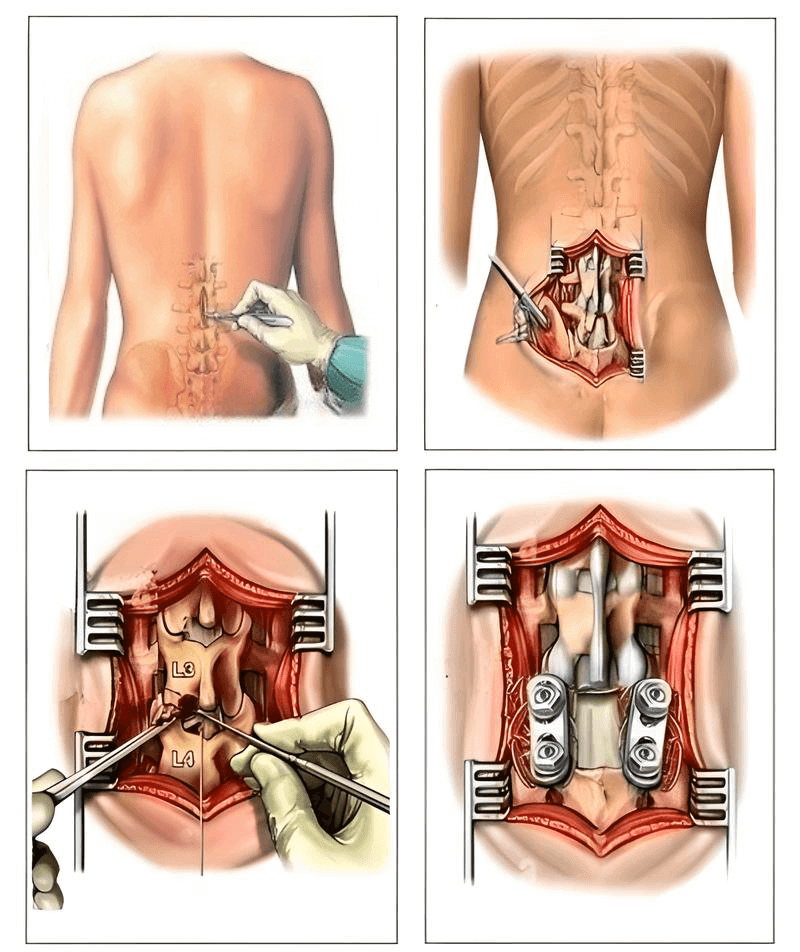

Jediné řešení, které může medicína nabídnout, je složitá a nebezpečná operace odstranění kýly a zavedení kovových tyčí! Ale třikrát si to rozmyslete! I nejlepší chirurgové přiznávají, že zákroky na páteři jsou velmi nežádoucí volbou, KTERÁ ČASTO VEDE K JEŠTĚ VĚTŠÍM PROBLÉMŮM, INFEKCÍM, KONTAMINACI, KOMPLIKACÍM A DOKONCE I SMRTI!

Odstranění kýly páteře se zavedením kovových tyčí je zákrok, který často

vede ke komplikacím: pravděpodobnost infekce, amputace nebo sepse se

zvyšuje o 60 %. Rehabilitace je dlouhá a bolestivá a riziko invalidity

je obrovské.

Odstranění kýly páteře se zavedením kovových tyčí je zákrok, který často

vede ke komplikacím: pravděpodobnost infekce, amputace nebo sepse se

zvyšuje o 60 %. Rehabilitace je dlouhá a bolestivá a riziko invalidity

je obrovské.

Důležité je poznamenat, že po odstranění kýly se ve 2/3 případů kýla vrátí během následujících 4 let, protože se neřeší příčina!

Pacienti po zákroku často ztrácejí nejen zdraví, ale i poslední naději na plnohodnotný život. Komplikace, chronická bolest, měsíce rehabilitace — to je jen začátek nové mučivé cesty! Úplné utrpení a omezení!